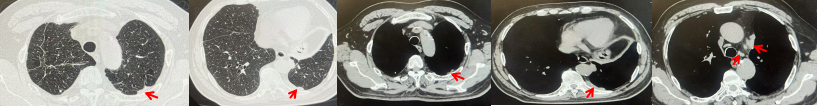

71岁男性,高血压病史20年,口服药物治疗,无糖尿病、心脏病等基础疾病,吸烟史50年,20支/天,已戒1年余,无饮酒史,无肿瘤家族史。2023.11因咳嗽、咳痰行胸CT检查:左肺下叶占位性病变,大小约12mmx8mm(如图5)。2023.11.20行“单孔胸腔镜左肺中下叶切除、肺门及纵隔淋巴结清扫、胸膜粘连松解术”;术后病理:(左肺下叶)结合免疫组化鳞状细胞癌(中、低分化),局部见脉管内癌栓,未见确切神经侵犯,(气管切缘)净。(淋巴结)未见转移癌0/19(4组0/1;5组0/1;6组0/2;7组0/1;9组0/1;10组0/2;11组0/3;12组0/2;13组0/2;14组0/4)。术后分期pT1bN0M0 IA期,术后定期复查。

图5:患者手术前(2023.11)胸部CT肺窗及纵隔窗

图6:患者胸膜及纵隔转移(2024.09)胸部CT肺窗及纵隔窗